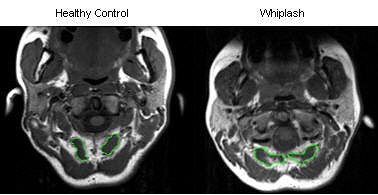

For the image analysis, regions of interest (ROI) were drawn over each bilateral cervical extensor muscle on the axial T1-weighted images at each vertebral segment (C0-C7). The authors also tested the reliability of MRI in this setting.

| T1-weighted MRI axial scan of C0-C1 (rectus capitis posterior minor outlined in green). |

According to the results, MRI showed a higher level of fat within all extensor muscles in the WAD group. Also in this group, the multifidus muscle showed significantly higher fat content at each level. The largest amounts of intramuscular fat were pinpointed in the rectus capitis posterior minor and major, and the deep cervical multifidi muscles, the authors stated.